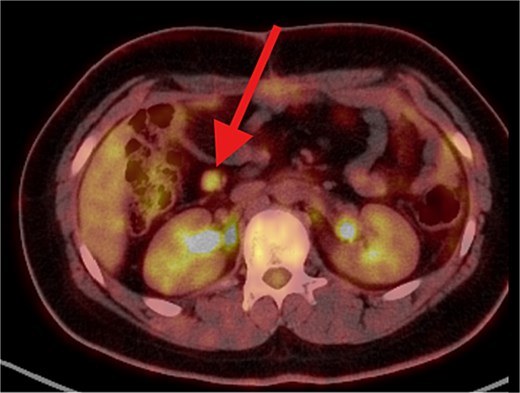

The patient underwent left lateral hepatectomy and cholecystectomy following diagnosis. Histopathology confirmed undifferentiated embryonal sarcoma (UES) of the liver with a 1 mm clear margin (Fig. 1); immunohistochemistry supported the diagnosis. The gallbladder showed chronic cholecystitis, and the lymph nodes were tumor-free. Postoperative imaging after two months revealed a recurrent mass near the stomach (Fig. 2), confirmed as recurrent UES by biopsy. Re-excision showed extensive necrosis and peritoneal infiltration. Positron emission tomography – computed tomography (PET-CT) later identified peritoneal and mesenteric metastases (Fig. 3). Follow-up PET-CT also revealed multiple small hypermetabolic hepatic nodules in addition to peritoneal and mesenteric lesions, indicating intrahepatic disease recurrence. Six cycles of chemotherapy resulted in near-complete resolution of metabolic lesions, with minimal residual activity. Follow-up imaging showed near-complete resolution of hepatic nodules, with only one residual, non-suspicious tiny nodule. After additional chemotherapy and targeted therapy cycles, PET-CT revealed new focal hypermetabolic activity near the splenic flexure, anterior to the spleen, raising concern for recurrence (Fig. 4). The patient underwent omentectomy and splenectomy. Histopathology confirmed metastatic UES in a 2.5 cm splenic lesion with hemorrhage and necrosis, and a 0.4 cm omental nodule, both completely excised. A total of 15 chemotherapy cycles were completed. Post-treatment imaging showed a mixed-density lesion in the splenic bed with FDG uptake, possibly post-surgical, and a new hypermetabolic mesenteric nodule (Fig. 5). Magnetic resonance imaging showed a cystic post-surgical collection without enhancing lesions. Subsequent imaging revealed regression of the splenic bed lesion and resolution of the mesenteric nodule; however, a new hypermetabolic mesenteric density emerged (Fig. 6). The lesion was placed under active surveillance, with additional chemotherapy administered and repeat imaging scheduled to assess response. Bilateral axillary lymph nodes showed reactive hypermetabolism. The patient, having undergone hepatectomy, splenectomy, and multimodal therapy, remains under close surveillance with encouraging treatment response.

PET/CT scan shows a clear surgical site (left subphrenic area) with no residual/recurrent mass, but there are multiple peritoneal and mesenteric nodules which appear to be hypermetabolic on PET scan, suggesting secondary metastasis.